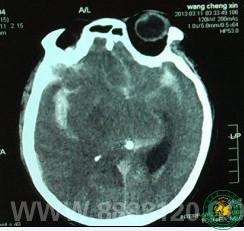

我科成功急诊夹闭颅内动脉瘤一例

我科成功急诊夹闭颅内动脉瘤一例3906